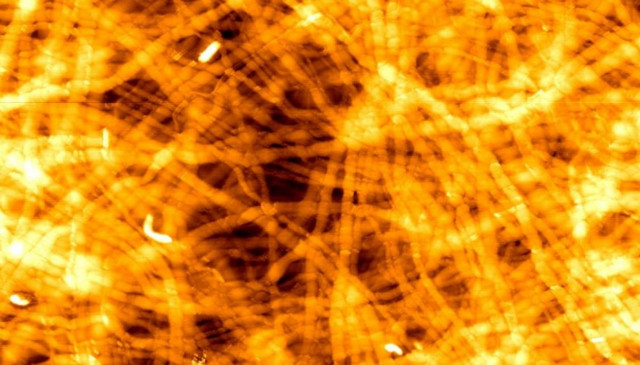

Το φως στην υπηρεσία της ιατρικής

Νέες εφαρμογές που αφορούν τη χρήση του φωτός στην έγκαιρη ανίχνευση του καρκίνου...

Νέες εφαρμογές που αφορούν τη χρήση του φωτός στην έγκαιρη ανίχνευση του καρκίνου, στην οδοντιατρική και στην αντιμετώπιση της νόσου του Alzheimer αναμένεται να χρησιμοποιηθούν στην συνάντηση 50 ειδικών επιστημόνων από όλη την Ευρώπη.

Αυτό το γεγονός θα λάβει χώρα στο Ινστιτούτο Ηλεκτρονικής Δομής και Λέιζερ του Ιδρύματος Έρευνας & Τεχνολογίας (ΙΗΔΛ-ΙΤΕ) στο Ηράκλειο Κρήτης, στις 27 Απριλίου και θα ολοκληρωθεί στις 29 Μαρτίου.

Συγκεκριμένα, η συνάντηση διοργανώνεται από την Photonics4life, μία πανευρωπαϊκή κοινοπραξία που χρηματοδοτείται από την Ε.Ε., συμμετέχουν συνολικά 13 Ιδρύματα-εταίροι και δημιουργήθηκε προκειμένου να ενδυναμωθούν οι δεσμοί μεταξύ των διαφόρων ομάδων που δραστηριοποιούνται στους τομείς των θετικών επιστημών και της ιατρικής.